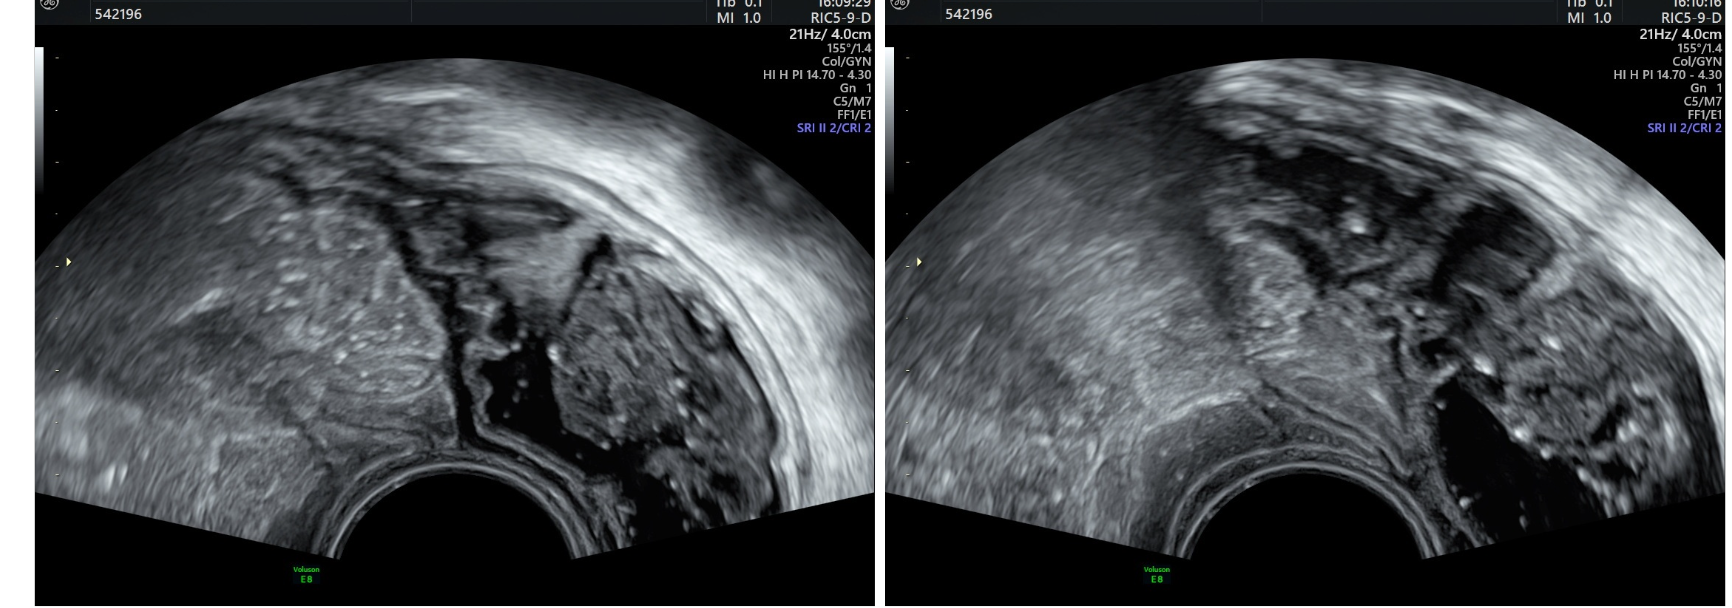

Elle permet de réaliser un premier bilan de réserve ovarienne et cavitaire dans le cadre de la PMA. L’échographie 3D permet la reconstruction dans les 3Dimensions de la cavité utérine ou d’une masse pelvienne.

L’hystérosonographie est une échographie endovaginale combinée à l’instillation de liquide dans la cavité utérine.

Elle permet d’étudier les anomalies endocavitaires de type fibrome, polypes ou synéchies.